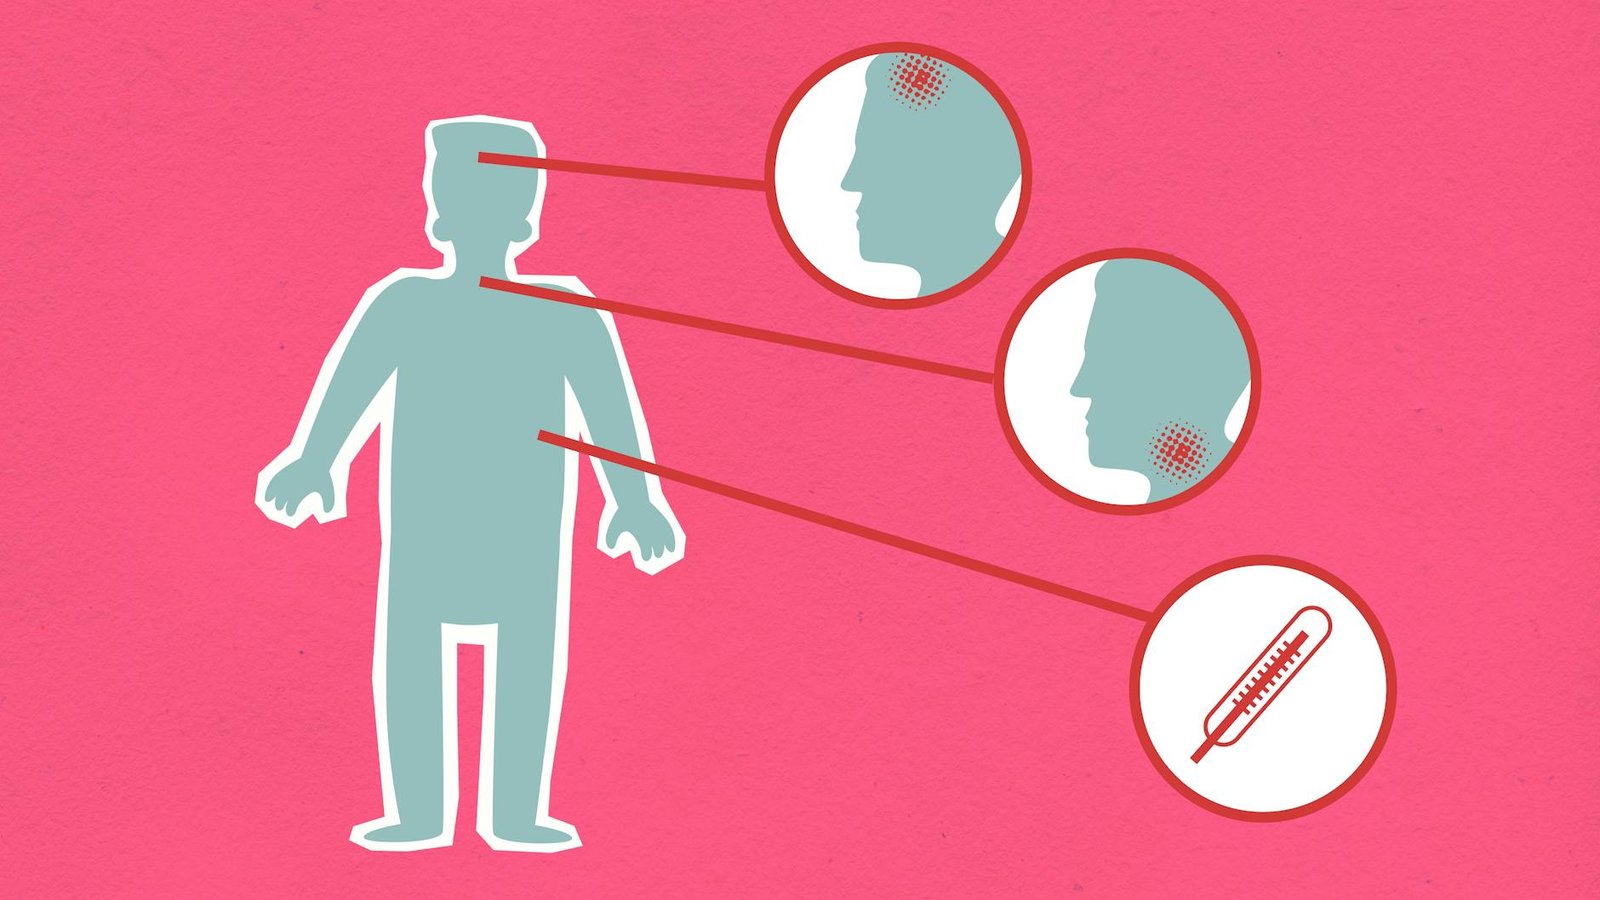

Ilgasis COVID: simptomai, gydymas ir ilgalaikės pasekmės

Ilgasis COVID: simptomai, gydymas ir ilgalaikės pasekmės